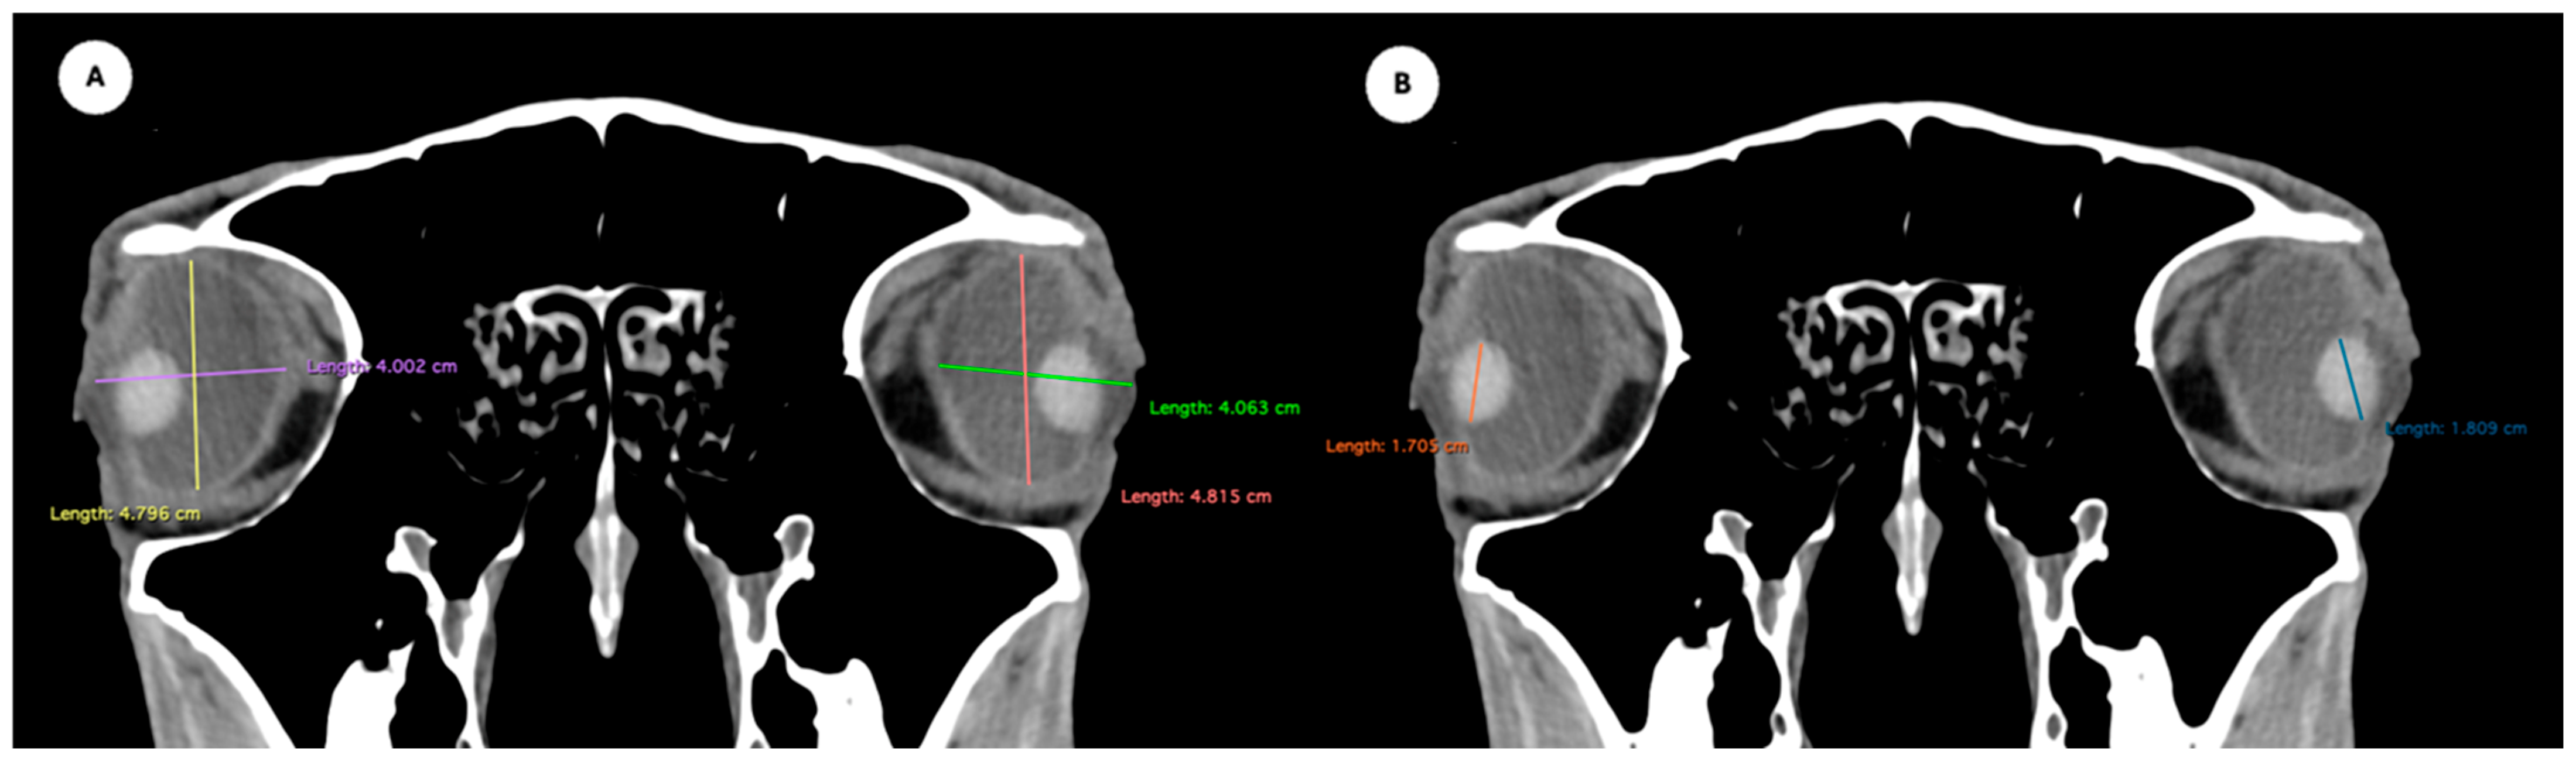

- Eyeball equatorial width and height: Maximal anterior–posterior distance (Figure 1A) and maximal lateromedial distance of the eyeball, measured perpendicular to the axial length (Figure 2B).

Figure 1. (A) Transverse multiplanar reconstruction (MPR) of the equine eyeball showing the maximum anterior–posterior distance (axial length), measured from the external surface of the cornea to the internal surface of choroid/retina/sclera, and the maximum latero-medial distance (equatorial width), measured perpendicular to the axial length. (B) Transverse MPR illustrating lens dimensions, with the latero-medial distance (equatorial width), measured at its widest point.

Figure 2. Dorsal multiplanar reconstruction (MPR) images showing (A) the maximal latero-medial distance of the lens and (B) the maximal latero-medial distance of the eyeball, measured perpendicular to the axial length, immediately caudal to the lens. - Orbital cavity height: Maximal dorsoventral distance of the orbital cavity at the level of the eyeball.

Table 1 provides summary statistics (mean, median, range, and standard deviation) for the internal ocular measurements of the left eye, right eye, and both eyes combined across all 20 horses. The average ocular measurements indicated that the eyeball height (5.19 ± 0.13 cm) was greater than its width (4.28 ± 0.12 cm), confirming the characteristic oval shape of the equine eye. The mean axial length was 5.09 ± 0.17 cm, consistent with previous descriptions of large-globe morphology in horses. The orbital cavity measured 5.27 ± 0.12 cm in height and 6.29 ± 0.14 cm in length. The anterior and posterior chambers had mean widths of 0.56 ± 0.07 cm and 2.26 ± 0.09 cm, respectively. The lens exhibited a mean height of 1.53 ± 0.06 cm, width of 1.23 ± 0.06 cm, and length of 1.63 ± 0.04 cm. These results collectively reflect the regular proportions and bilateral symmetry of the equine eyeball and its internal structures, as detailed in Table 1. The Mann–Whitney U test revealed no statistically significant differences in the measurements between the right and left eyes. Similarly, when all variables were considered collectively, the analysis confirmed the absence of significant differences between both eyes